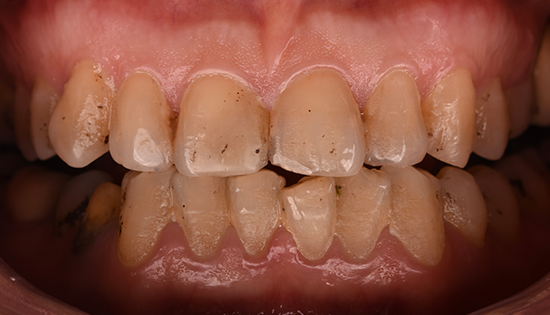

يلجأ الشخص إلى تحسين شكل أسنانه عن طريق فينير الأسنان أو ما يطلق عليه (عدسات الأسنان اللاصقة) وهي عبارة قشرة رقيقه يتم لصقها على السطح الخارجي للأسنان مصنوعة من مواد صلبة ذات معامل شفافيه مطابق للأسنان الطبيعيه   لعلاج مشكلة الاصفرار أو عدم التساوي والعديد من المشاكل الأخرى، حتى يحصل الشخص على ابتسامة رائعة تشبه ابتسامة نجوم هوليود.

•  تغير لون الأسنان الطبيعية من اللون الأبيض للون الأصفر.

• وجود مسافات بين الأسنان.

• تكسر وتشقق الأسنان.

• عدم تناسق الأسنان او اعوجاجها.

• وجود حشوات عديده بالأسنان الأماميه ذات مظهر سيء.